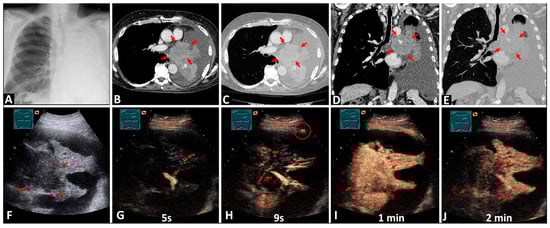

3.2.1. Differentiation between the Tumor and Atelectatic Tissue on B-US

3.3.1. Differentiation between the Tumor and Atelectatic Tissue on CEUS